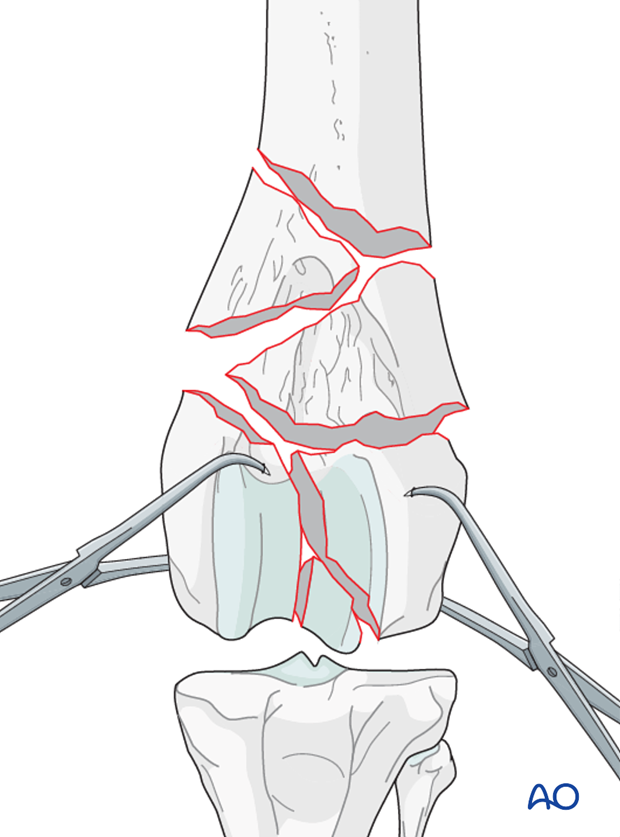

The articular fracture of the condyles is reduced with pointed reduction forceps. Anatomic reduction is essential in all cases.

Note: Bone in juvenile patients is very soft. Care must be taken not to damage it during reduction.

The reconstructed femoral condyles are carefully reduced to the metaphysis with pointed reduction forceps. Anatomic reduction is desired in all cases. Under-reduction of the fracture should be avoided as it is less stable, and the cranial aspect of the metaphysis may interfere with the gliding of the patella in the trochlear groove.